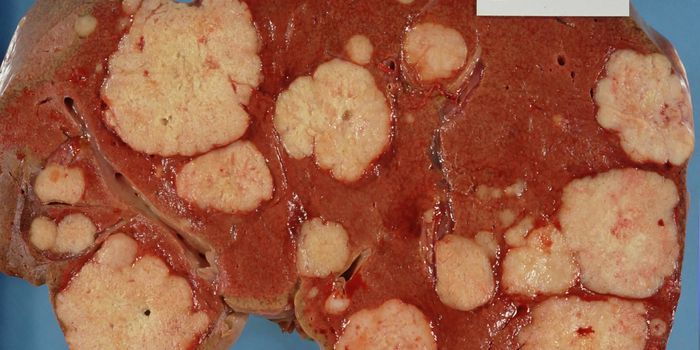

OCT 21, 2020CancerHepatocellular carcinoma, aka liver cancer, is an ever-increasing issue in the western world. While the lion’s sha ...